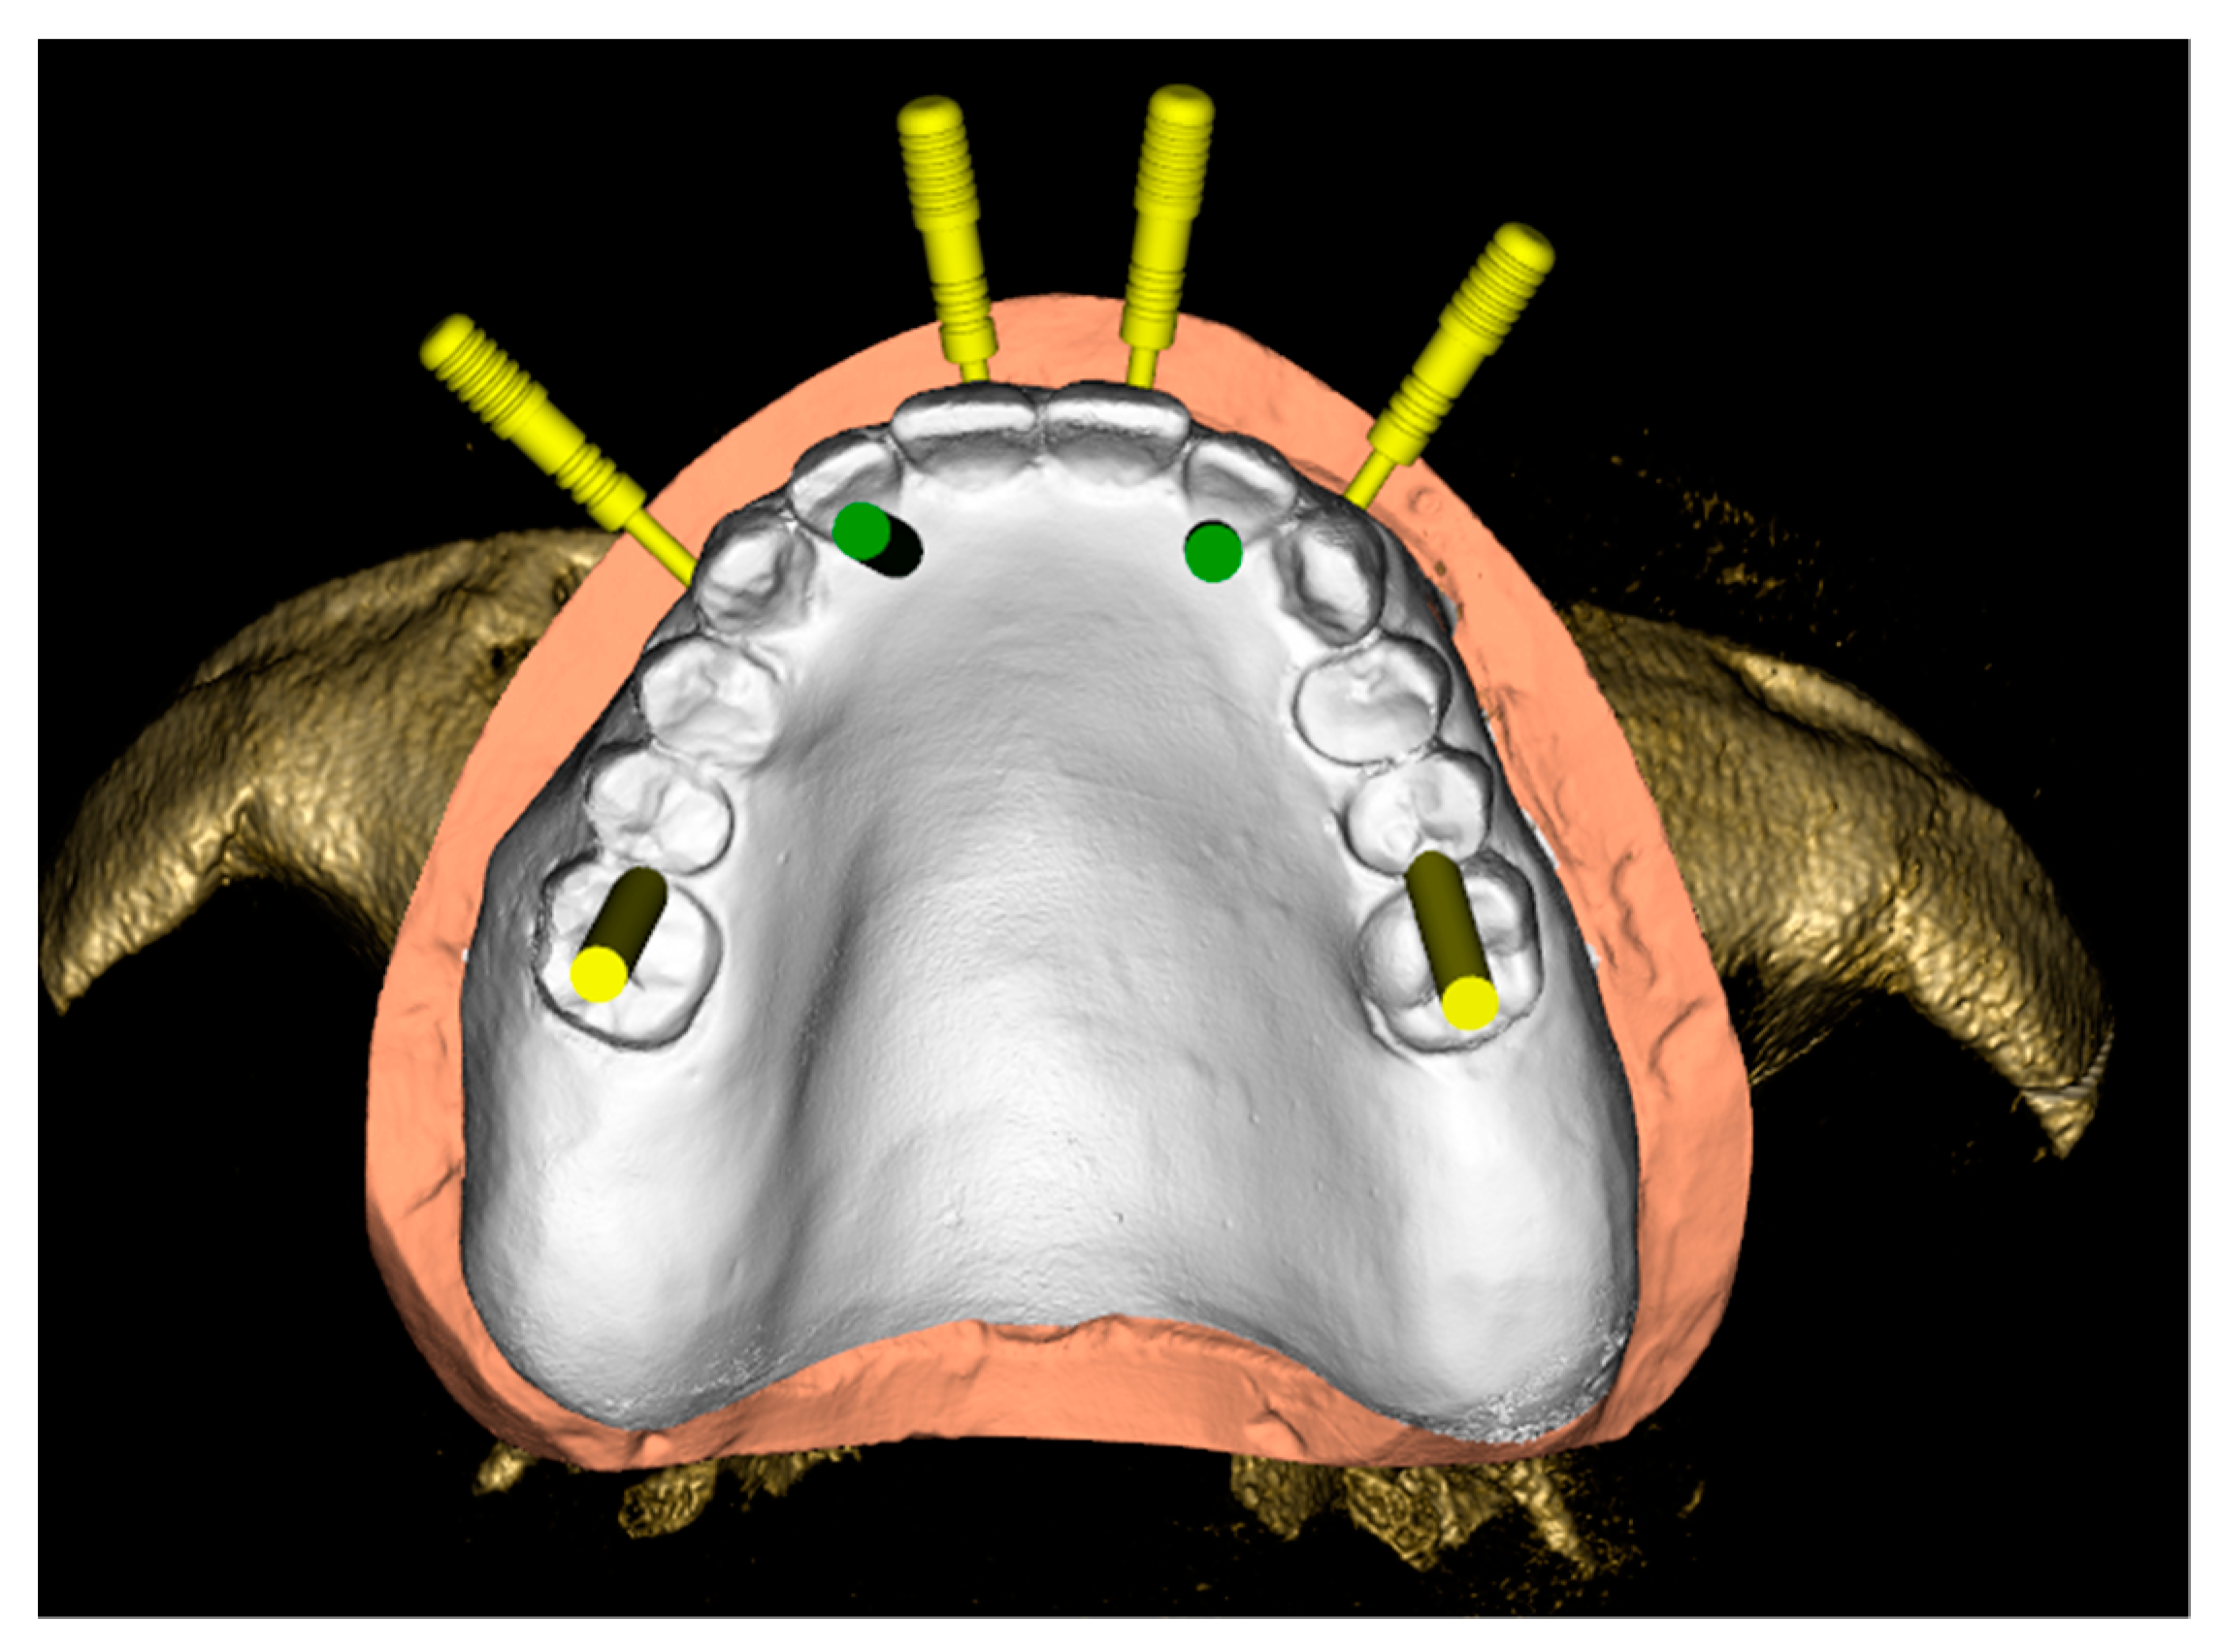

2.2.5. Third Appointment (Digital Protocol)

2.2.6. Fourth Appointment (Digital Protocol)

2.2.7. Fifth Appointment (Digital Protocol): Surgical Phase and Immediate Loading Prosthesis

2.2.8. Final Prosthesis